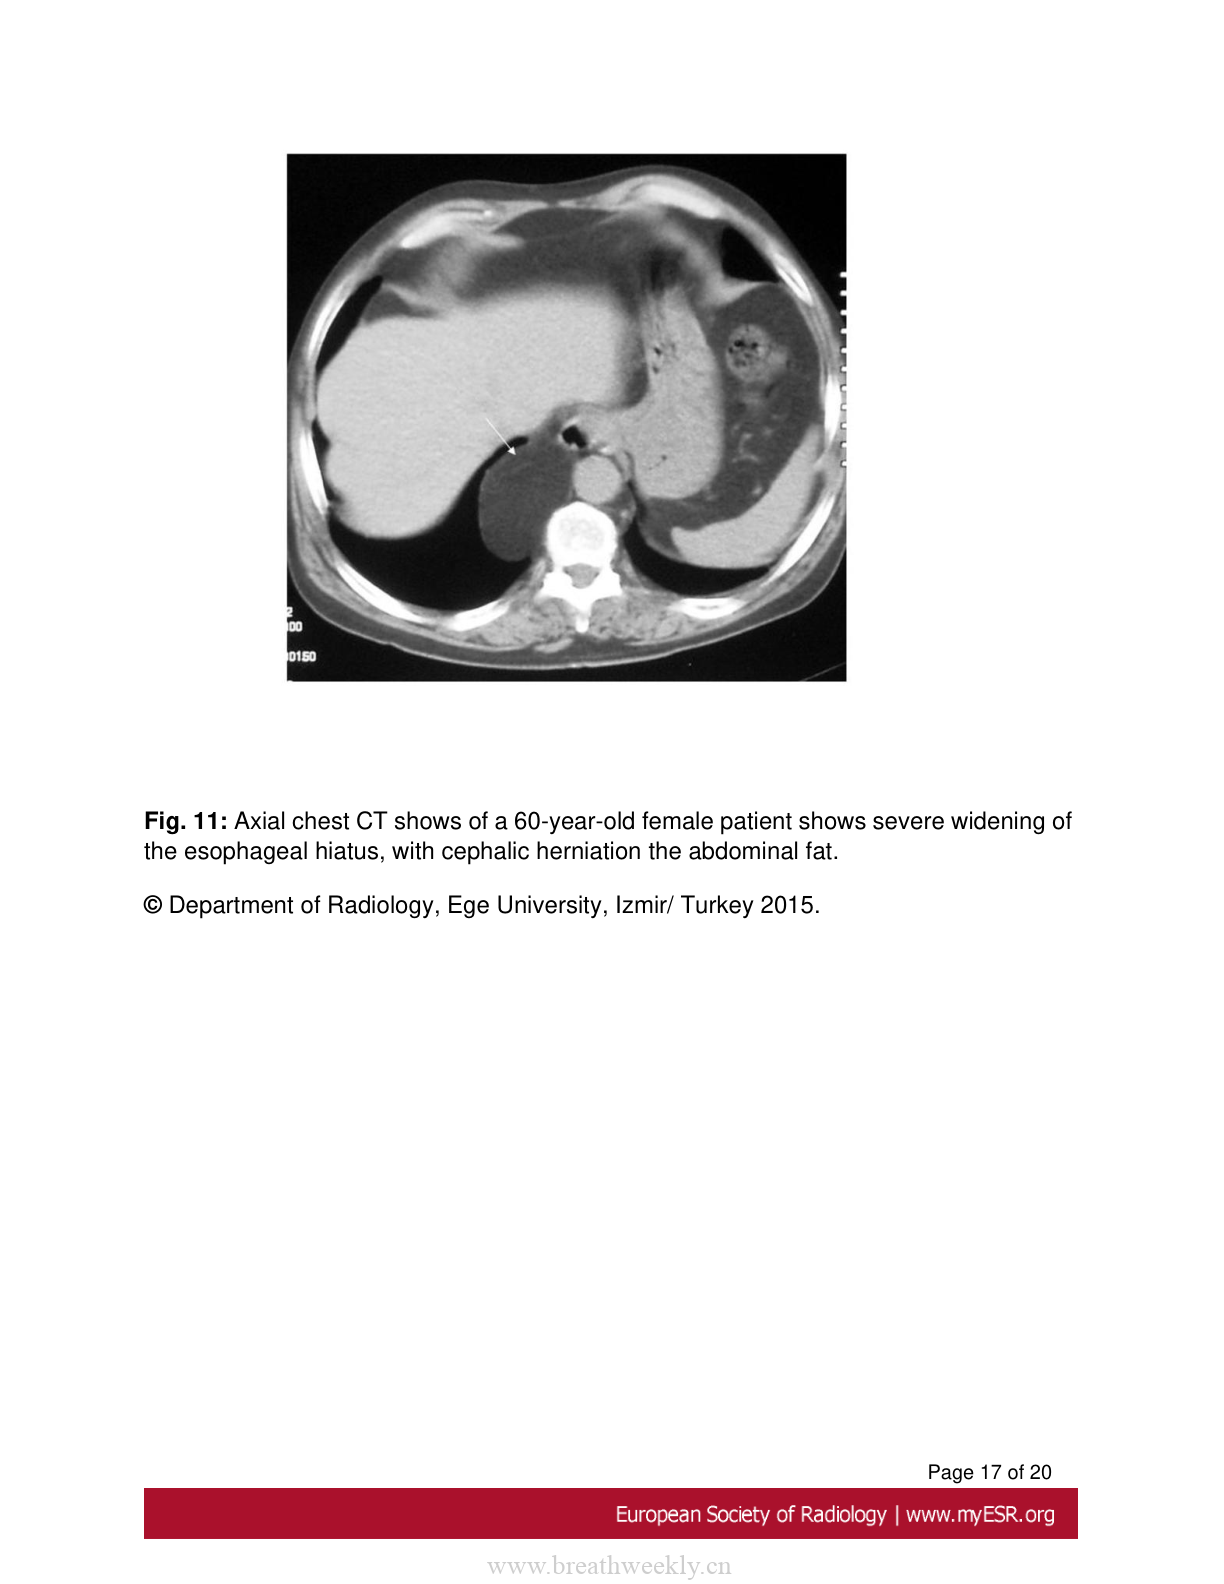

图11:食管裂孔疝

60岁女性患者的轴位胸部CT显示食管裂孔严重增宽,腹部脂肪向头侧疝入。